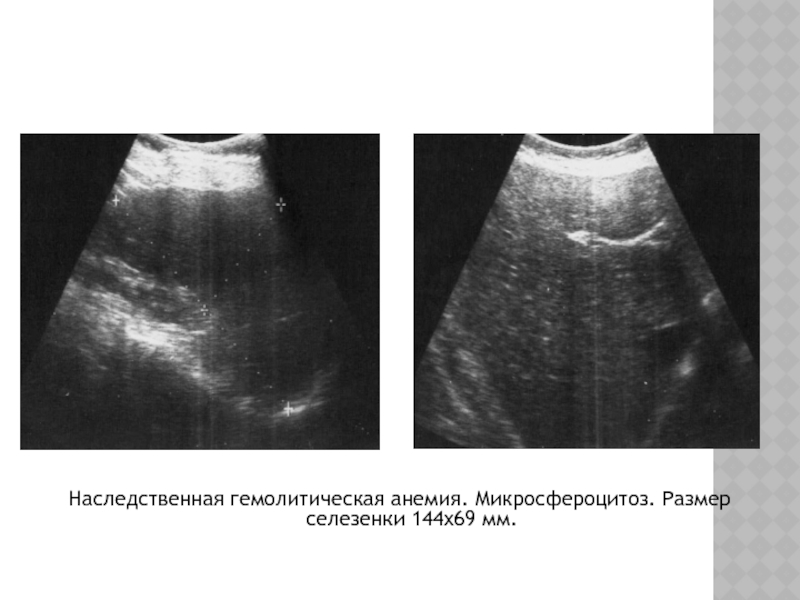

Слайд 21Наследственная гемолитическая анемия. Микросфероцитоз. Размер селезенки 144х69 мм.